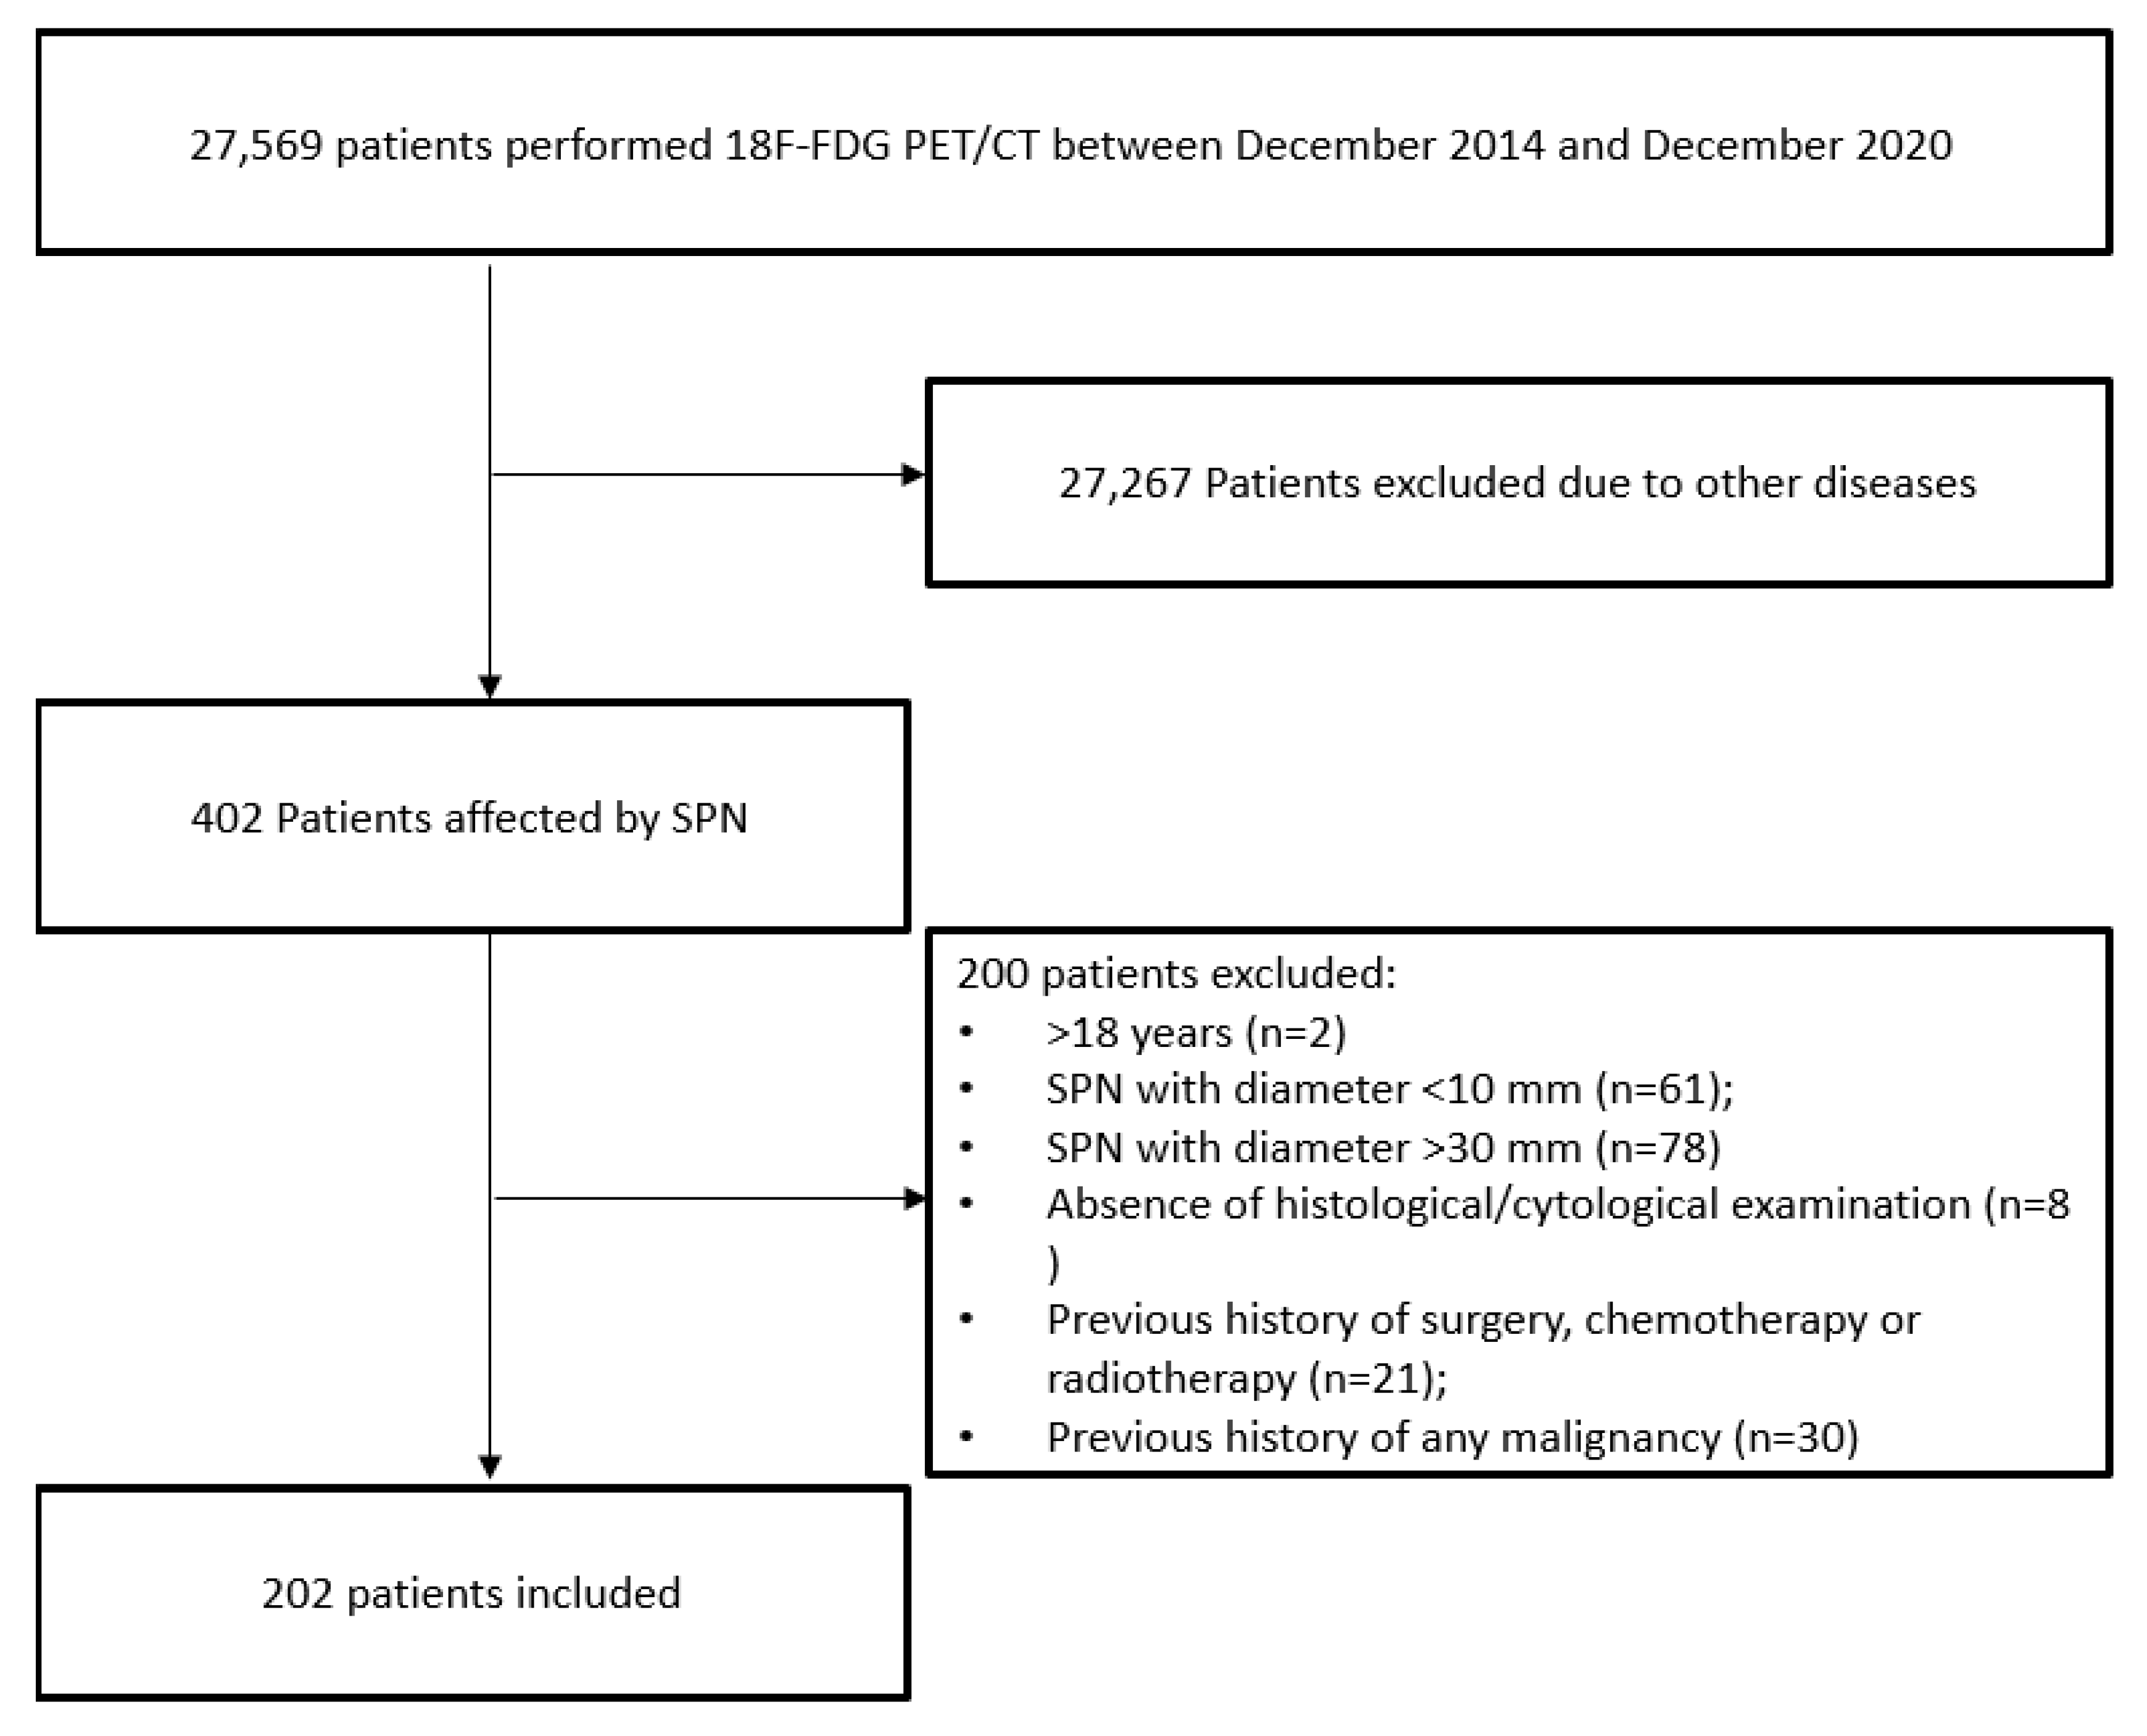

2.1. Patients